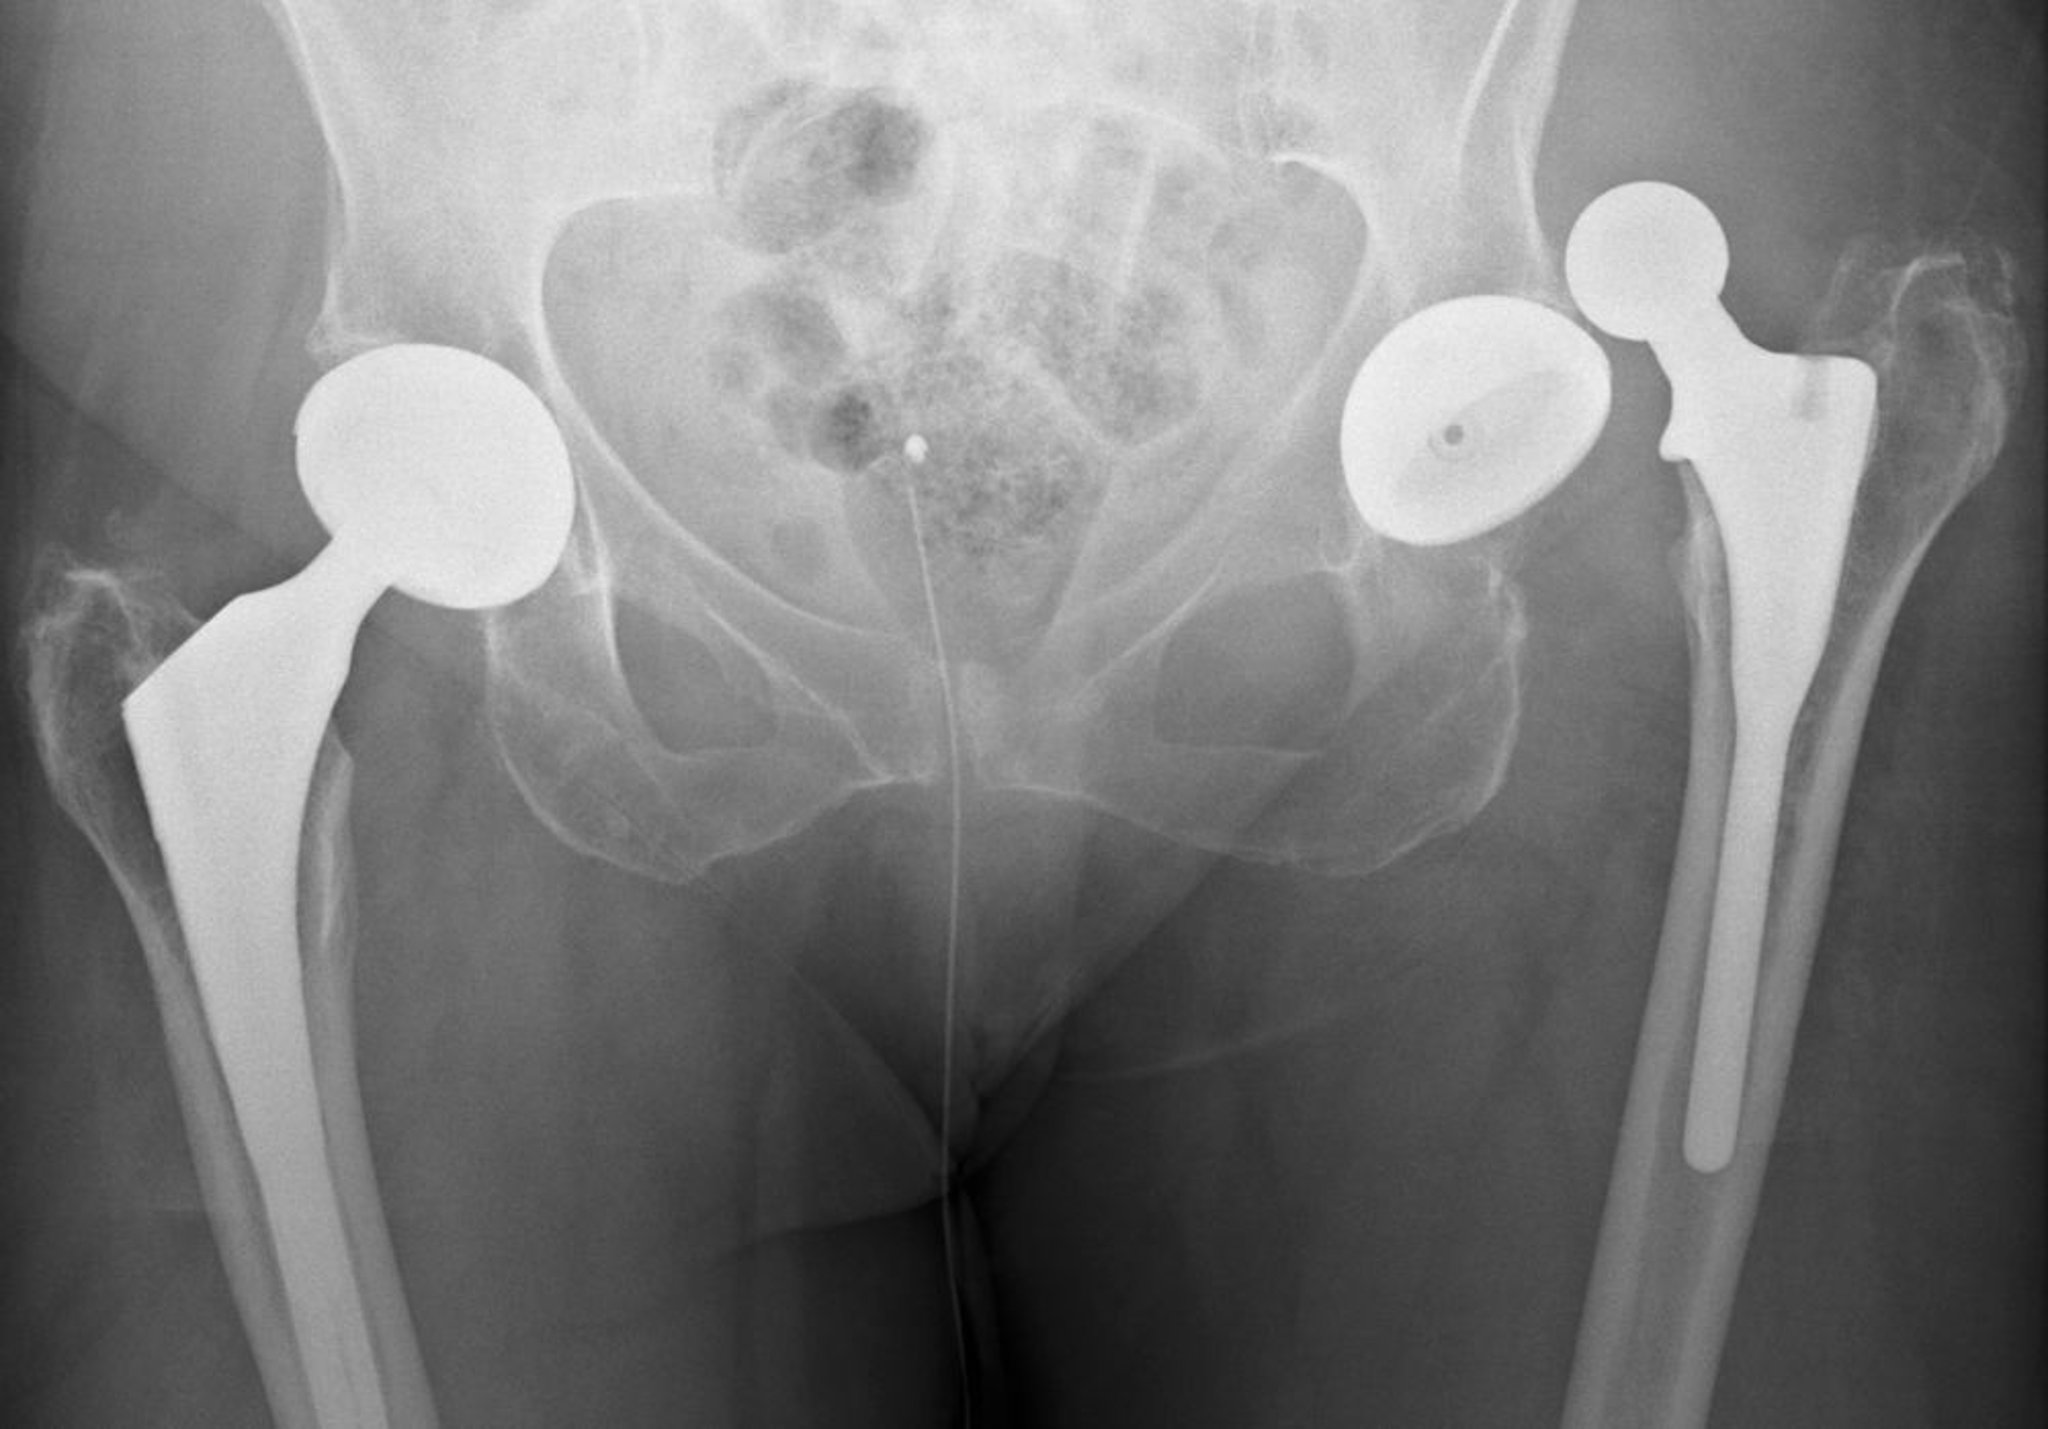

Вывих протеза тазобедренного сустава

Это задний вывих.